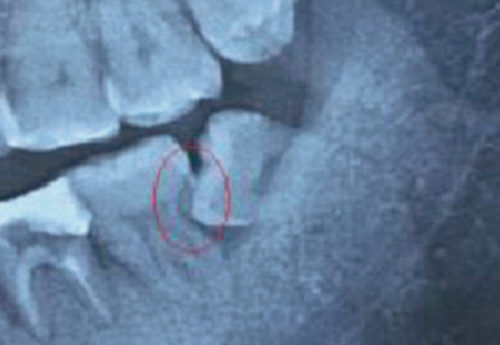

Jei protiniams dantims nėra galimybės tinkamai išdygti, nustatomas dantų susigrūdimas – tokia situacija yra ganėtinai pavojinga, nes susigrūdę dantys gali sukelti infekciją, lemti gretutinių dantų gedimą, dantenų ligas ar cistų formavimąsi. Kai siekiama išvengti šių problemų, odontologai rekomenduoja protinius dantis pašalinti. Prieš tai yra atliekama rentgeno nuotrauka, kuri padeda nustatyti dantų rovimo būtinybę.

Taip yra yra vadinami įstrigę arba nedygstantys protiniai dantys, kurie gali būti visiškai susiformavę, tačiau taip ir neišdygę. Odontologai skiria du pagrindinius protinių dantų retencijos laipsnius:

Esant šiai patologijai odontologai dažniausiai pataria tokius dantis pašalinti, nes priešingu atveju tai gali sukelti tam tikrų komplikacijų, kurių dažniausios yra šios: